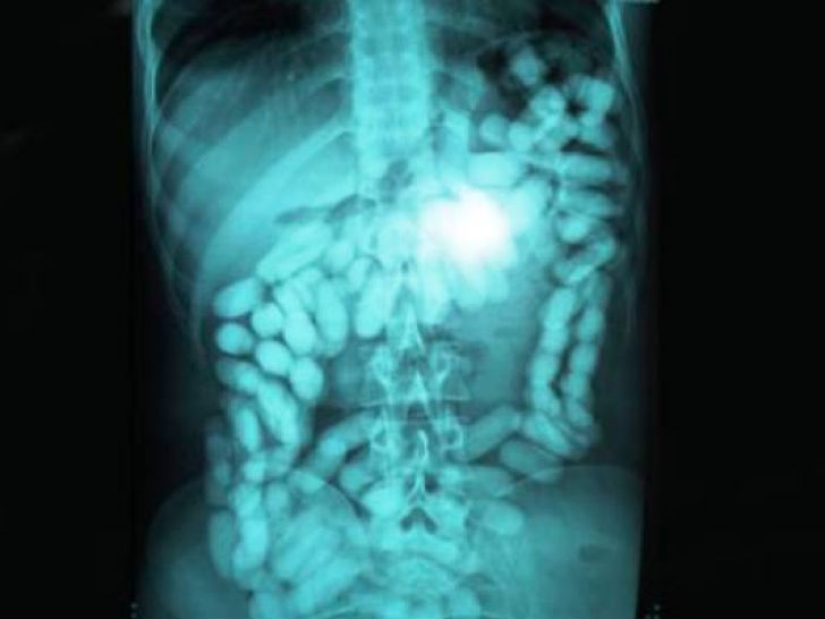

Y esta es la foto de un hombre que ingirió una cantidad considerable de drogas para traficarlas a través de la frontera.